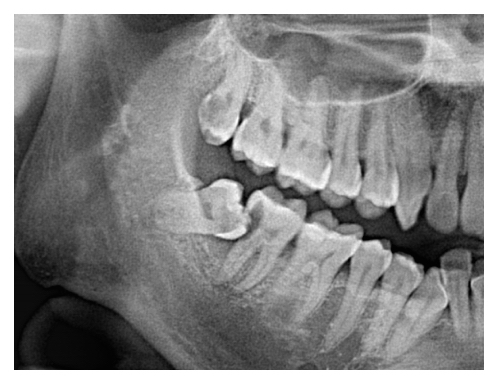

Fig 1 : Pre-operation x-ray shows impacted wisdom tooth